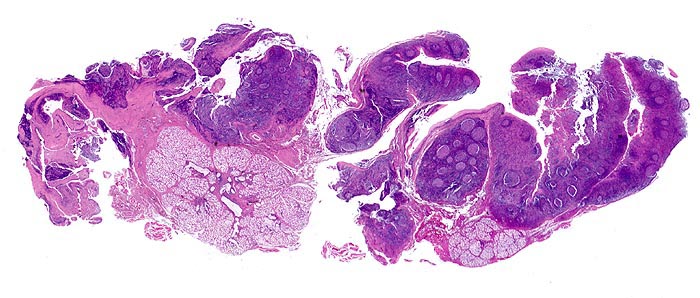

PathoPic ID 4017 - infektiöse Mononukleose

infektiöse Mononukleose

Entzündung infektiös

Tonsille

Lymphatische Gewebe, KM, Milz

Aktivierung der B-Lymphozyten-Areale (EBV induzierte Infektion und Stimulation der EBV-Rezeptor tragenden B-Zellen): grosse, aktivierte Keimzentren (=

follikuläre Hyperplasie).

Aktivierung der T-Lymphozyten-Areale (Virusantigen-induzierte Aktivierung der spezifischen antiviralen T-Zell Antwort):

interfollikuläre Hyperplasie.

Speicheldrüsen.

Tonsillektomie bei einem Studenten mit Angina, Lymphknotenschwellungen und einer Lymphozytose im Blut.

Histologie

Scan

16

männlich